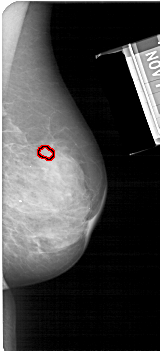

FILE: A_1683_1.RIGHT_CC.OVERLAY

TOTAL_ABNORMALITIES 1

ABNORMALITY 1

LESION_TYPE MASS SHAPE OVAL MARGINS OBSCURED

ASSESSMENT 3

SUBTLETY 3

PATHOLOGY BENIGN

TOTAL_OUTLINES 1

BOUNDARY